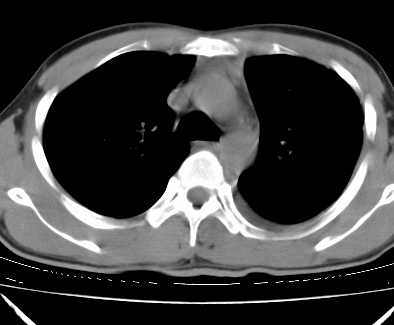

二周前患者无明显诱因出现咳嗽,多为刺激性干嗽,无咯血,伴心悸,低热,夜间无明显盗汗,消瘦明显

年龄?左侧胸腔中量积液,左下肺见有较多斑片状和大片状影,伴有支气管充气征,考虑:1、左下肺炎;2、结核。肿瘤可以基本排除。

考虑:1、左下肺结核左侧胸腔中量积液,心包积液纵隔肿大淋巴结.

考虑:1、左侧中量胸腔积液伴左肺下叶肺膨胀不全、炎症。

2、心包积液。

左下肺见有较多斑片状和大片状影,支气管通畅,左侧胸腔积液,考虑:左下肺炎伴胸腔积液

左侧中量胸腔积液伴左肺下叶肺膨胀不全、上肺外围多个小囊样腺泡样病灶。考虑化脓炎症。

心包积液没有,纵隔积液。

纵隔肿大淋巴结不明显。

1、左侧中量胸腔积液伴左肺下叶肺膨胀不全、。

3 无纵隔肿大淋巴结.

患者刺激性干嗽,无咯血,伴心悸,低热,夜间无明显盗汗,消瘦明显,左侧中量胸腔积液伴左肺下叶肺膨胀不全、上肺外围多个小斑片病灶。考虑肺结核可能性大。

左肺舌叶及下叶见斑片状,大片状高密度影并相应处胸膜及心包不规则增厚,左肺下叶膨胀不全。右肺未见异常,双肺段以上支气管通畅。纵隔左移,其内未见明显肿大淋巴结。左侧胸腔积液。

1.考虑:左肺化脓性炎症。2.左侧胸腔积液(中等量)。3.心包炎症。